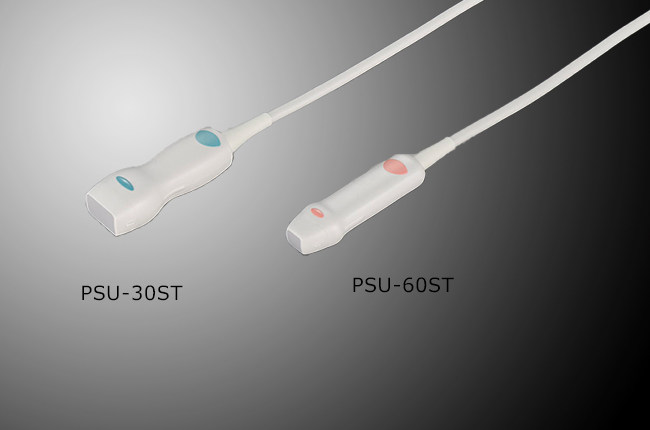

Підтримка широкої лінійки широкополосних мультифокальних датчиків з частотою до 14 MHz.